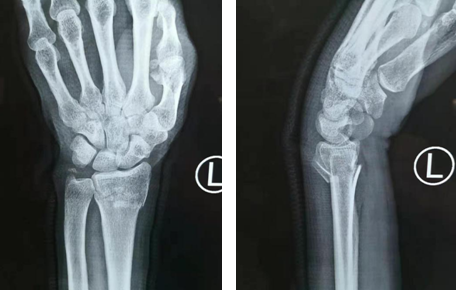

经过进一步检查,证实了齐主任的判断。

片子显示,骨头碎裂